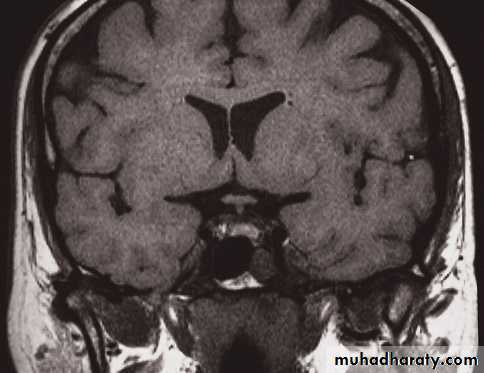

MRI of the brain

• Axial, coronal and sagittal projections are all considered standard• T1-weighted and T2-weighted images.

• It is possible to recognize flowing blood and, therefore, the larger arteries and veins stand out clearly without the need for contrast medium.

• The characteristics of grey and white matter are different, and both are clearly different from the CSF in the ventricular system and subarachnoid space.

• The disadvantages of MRI compared with CT are the inability to show calcification, lack of bone detail, the relative expense of the technique, and the difficulty of monitoring seriously ill patients